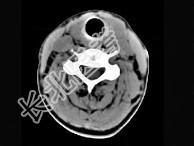

- 单项选择题40岁,女性患者, 双侧甲状腺肿大,CT扫描如图所示, 请选择最佳答案 ( )

A、弥漫性甲状腺肿

B、甲状腺癌

C、甲状腺炎(桥本)

D、亚急性甲状腺炎

E、甲状腺瘤